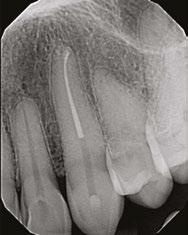

Judy McIntyre, DMD, MS Figure 1: Acutely curved and calcified buccal canal right under upper left premolar crown margin; valuable information for access and management. No. 9 also has a PARL, which was only incidentally captured Figure 2: Large PARL with destruction of the maxillary sinus floor and sinusitis as a result

About 10 years after completing residency, I opened my own practice and invested in a DEXIS CBCT. Initially, I only used it for apicoectomies and retreatments. In time, I began to realize how helpful it was for all my cases. With the 3D-scan information (Figure 1), I could have saved myself some humbling experiences and surprises. Endodontists hate surprises, and we really hate failures! Once I started using my CBCT more frequently, I was able to appreciate things that would have otherwise been intra-op surprises and plan for them prior to starting the procedure. The 3D data allows me to properly assess prognosis, determine the best course of treatment, and plan that treatment with a level of precision that is impossible otherwise.

Figure 3: Second maxillary molar with external root resorption (ERR) with incidentally captured ERR on the lower mandibular first molar as well. When there is one tooth with resorption, be suspicious of other teeth with resorption, especially on younger patients Figure 6: No PARL on PA film. Clear PARL on scan taken with medicament Figures 4 and 5: 4. Mandibular molar with a J-shaped lesion due to endo — not a vertical root fracture. Path of least resistance happens to be through a distal perio pocket, but this is an endo-perio lesion and not a VRF. Incidentally, a mucous retention cyst was captured in the sinus. 5. Healing after bridge removal and retreatment

Figure 7: Planned-for access with the scan info on this extremely calcified canine Figures 8 and 9: 8. Deep distal split with PARL. 9. Missed buccal canal; history of previous RCT, post, crown and apico Figure 10: Retreatment consultation. PA from GD Figure 11: Scan images show a previously existing strip perforation